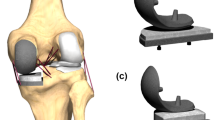

FB and MB unicondylar knee prosthesis designs were tested in sequences under isokinetic extension in an in vitro simulator, which can simulate muscular traction power using hydraulic cylinders, which cross over the knee joint. Thus, a knee movement like in a seated leg extension machine can be simulated. The kinemator (Fig. 1) has been described and used in a number of previous studies investigating knee biomechanics [7, 14, 15, 24]. In our study, 12 fresh frozen cadaver knees (64–78 years of age) with intact soft tissue, no previous surgery and no significant arthritis were randomised into one of two groups: (1) FB medial slide (Sigma® High Performance Partial Knee; DePuy, Warsaw, IN, USA); and (2) MB slide (Oxford® medial unicompartmental knee, III generation; Biomet, Warsaw, IN, USA). In each case, the required quadriceps extension force was determined before and after implantation of a medial UKA. Furthermore, the tibiofemoral contact pressures were evaluated for both prosthesis designs.